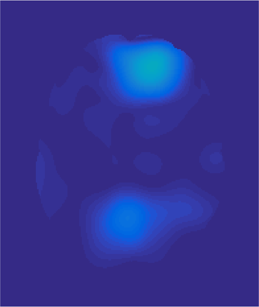

(a) (b) (c) (d) (e)

Fig. 3: Example atlas-to-image registration errors [mm]: (a) tumor; (b) LRS; (c) PCA model w/o regularization; (d) PCA model w/ one step of regularization; (e) PCA model w/ two steps of regularization.

Fig. 2 shows atlas-to-image registration results for images with and without tumor, LRS reconstruction and our PCA-based models with and without regularization. Fig. 3 shows the spatial error distributions, compared to the ground truth registration. We use NiftyReg [17] (with standard settings) and NCC for registrations. Errors are computed using Euclidean distance. Direct registration of the tumor image results in large registration errors. Registration to the low-rank reconstruction greatly reduces the error in the tumor areas but retains errors near the cortex, mainly due to its blurry reconstruction. Our PCA models further reduce registration errors in the tumor areas and keep errors near the cortex low.